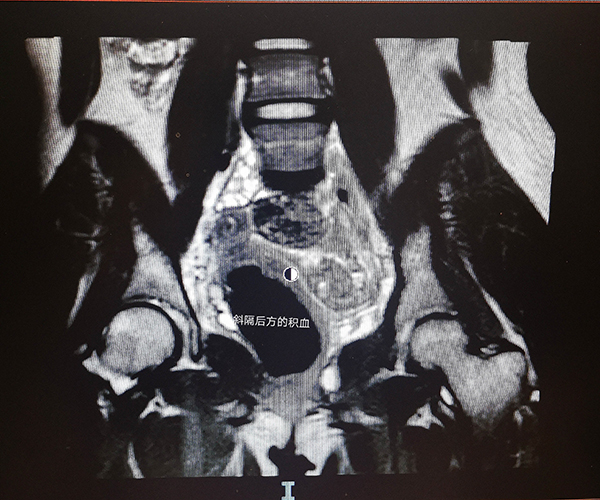

經過一番解釋,媽媽和孩子對疾病有了了解,決定進行手術治療。楊嵐副主任醫師對該類疾病有著豐富的臨床經驗,經過認真地查體和磁共振影像評估,她帶領團隊制定了周詳的手術計劃,最終成功為小龍實施了“陰道成形術+陰道斜隔切除術”。打開了封閉的隔墻,約500ml粘稠的積血“奔涌而出”,仔細“拆除”了圍墻后,宮腔鏡檢查雙側宮頸形態和宮腔都恢復正常,手術取得了滿意的效果。